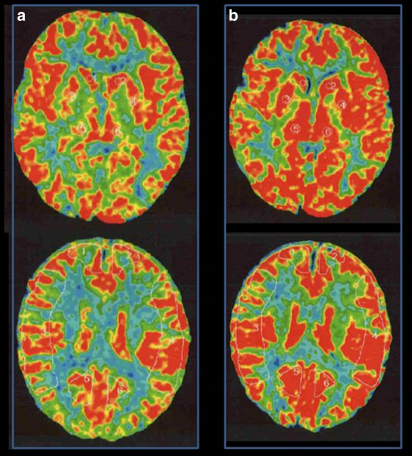

术前Xe-CT显示静息状态无偏侧(a),注射丹木斯(Diamox)后右侧MCA区域脑血管反应性为14.8%(b)。